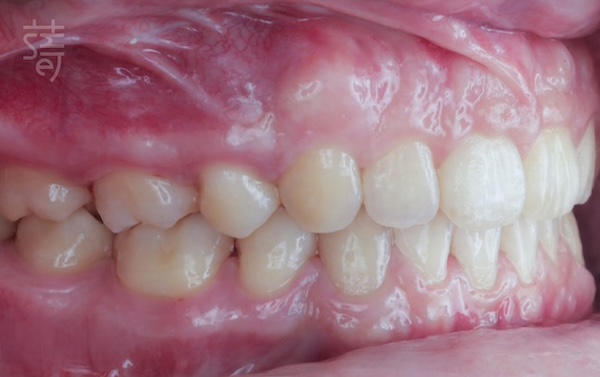

隨著時間推移,矯正成果一點一滴地顯現出來。

在隱適美鑽級醫師團隊的細心規劃與陪伴下,

鄭老師的暴牙與小下巴問題逐漸改善,

拔牙後所創造的空間也讓牙齒排列變得更加整齊

臉部比例也隨之變得更加協調,

笑容中多了一份從容與自信。